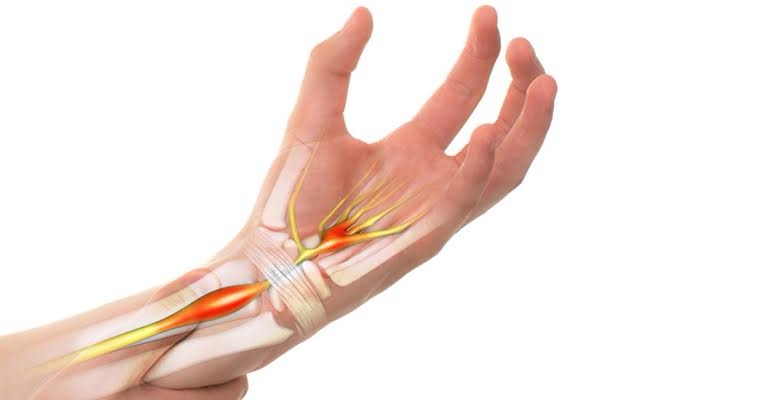

Esta síndrome causa formigamento, sensação de agulhas sendo “colocadas” no polegar indicador, anelar ou dedo médio. Trata-se da compressão do nervo mediano que passa pelo punho e inerva até a palma da mão.

Os sintomas da síndrome do túnel do carpo costumam piorar com o tempo, sendo bastante intensos durante o período noturno. É comum que acometa pessoas que fazem movimentos repetitivos das mãos diariamente, mas podem surgir por conta das fraturas na região ou até mesmo devido doenças crônicas, como problemas autoimunes e diabetes.